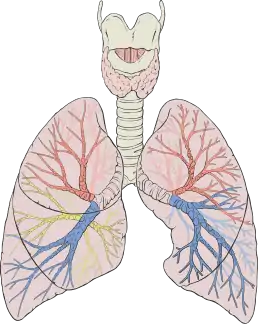

![]() شكل يوضح الرئتين البشريتين ضمن السبيل التنفسي، وقد تم تلوين كل فص بلون مختلف عن الآخر. | |

للإنسان رئتان، يمنى ويسرى، وتقع كلا الرئتين داخل التجويف الصدري. يُذكر أن الرئة اليُمنى أكبر من اليُسرى، وذلك لأن اليسرى تتقاسم مساحتها مع القلب. تزن الرئتان معًا قُرابَةَ 1.3 كيلوجرام، وتكون الرئة اليُمنى أثقل عادةً. تُعتبر الرئتان جزءًا من السبيل التنفسي السفلي، الذي يبدأ بالرغامى التي تتفرع فيما بعد إلى القصبتين والقُصَيبَات، وتتلقى القُصَيبات الهواء المُستَنشَق عبر المنطقة التوصيلية من السبيل التنفُّسيّ، حيث تنتهي المنطقة التوصيلية من السبيل التنفُّسيّ إلى القُصَيبَات الانتهائية، تنقسم فيما بعد هذه القُصيبَات الانتهائية إلى قُصيبات تنفسيّة وهنا تبدأ المنطقة التنفسيّة، تنقسم فيما بعد القُصيبات التنفسيّة إلى قنوات سنخيّة تعطي فيما بعد أسناخ مجهريّة، حيث يحدث التبادل الغازي، كما وتحتوي الرئتان معًا قُرابةَ 2400 كيلومتر من الطُرُق التنفسيّة و300 إلى 500 مليون سنخ. تقع كل رئة ضمن كيس جَنْبِيّ، يحتوي الكيس على سائل يسمح للجدران الداخلية والخارجية بالانزلاق أثناء حدوث التنفُّس مما يُخفِّف كثيرًا من الاحتكاك. يقسم كل كيس كل رئة إلى أقسام تُدعى بالفصوص. للرئة اليُمنى ثلاثة فصوص أما اليسرى ففَصَّان فقط. كما وتنقسم الفصوص بدورها إلى قطع قصبية رئوية وفُصَيصَات. للرئة ترويَة دمويَّة فريدة، حيث أنها تتلقى دمًا غير مؤكسج (قليل الأكسجة أو فقير بالأوكسجين) من القلب عبر الدوران الرئوي وذلك بغرض أكسجته وإطلاق ثنائي أوكسيد الكربون، بالإضافة إلى التروية السابقة فإن نسيج الرئتين تتلقى دمًَا مكسَجًَا (غنيّ بالأوكسجين) منفصلًا عن السابق وذلك عبر الدوران القصبي.

تقع الرئتان في الصدر على كل جانب من القلب داخل القفص الصدري. للرئة شكل مخروطِيّ ولها قِمَةٌ مدوَّرة متضيِّقَة في الأعلى وقاعدة مُقَعَّرَة واسعة تقع فوق سطح محدب للحجاب الحاجز.[2] تمتد قمة الرئة حتى جذر العُنُق، لتصل إلى ما فوق مستوى النهاية القَصِيَّة للضلع الأولى بقليل. تمتد الرئتين بدءًا من قُرب العمود الفَقَرِيّ في الخلف إلى مُقَدِّمَة الصَّدر في الأمام ومن الجزء السفلي للرغامى في الأعلى إلى الحجاب الحاجز في الأسفل.[2] تتشارك الرئة اليُسرَى مساحتها مع القلب، ولها في حافتها ثَلَمِة (أو أخدود) يُدعى الثَلَمِة القلبيّة للرئة اليُسرَى، وهي عبارة عن تضريس في حافة الرئة اليُسرَى يتوافق مع القلب.[3][4] تُوَاجِهُ السُطُوح الأمامية والخارجية للرئتين الأضلاعَ، مما يترك تضاريس خفيفة (انطباعات) للأضلاع، بينما تواجِهُ السطوح الأُنسِيّة للرئتين القَلبَ والأوعية الكبيرة والجُؤجُؤ (مكان انقسام الرُغَامى إلى قصبتين رئيسيَّتَين).[4] أما ما يُعرَف بالانطبَاع القَلبِيّ فهو تضريس يتشكَّل على سطوح الرئتين التي تواجه القَلب.